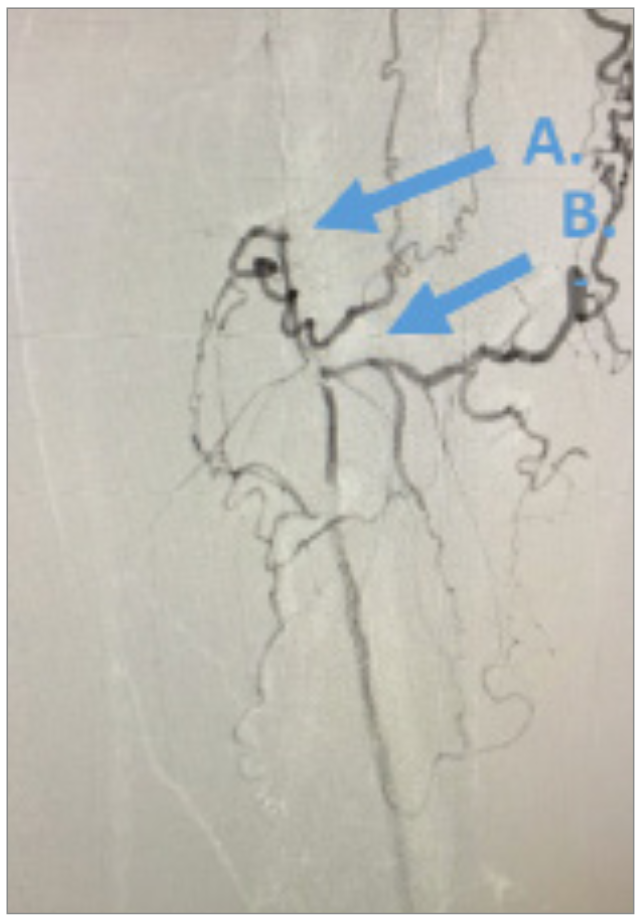

Angiography revealed that the superficial femoral artery (SFA) was occluded in the proximal segment with a short nub (Figure 1) and reconstituted in the mid segment by the profunda collaterals (Figure 2), before becoming reoccluded shortly thereafter and reconstituting in the distal SFA by the profunda collaterals (Figure 3). The P1 and P2 segments of the popliteal artery were patent, but the P3 segment had a short occlusion. The posterior tibial artery and peroneal artery also were patent.